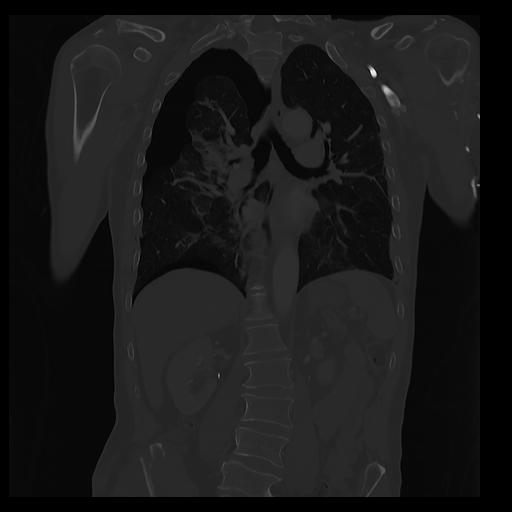

32 PULMON,CE,Coronal,3.000,PULMON,Coronal,